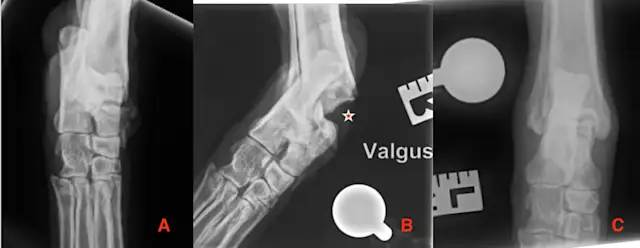

Plain orthogonal radiographs, including mediolateral oblique views (ie, dorsolateral-palmaromedial oblique, dorsomedial-palmarolateral oblique) and dorsopalmar or dorsoplantar views(Figure 4), should be obtained for lameness localized to the distal limb for confirmation of joint effusion, soft-tissue swelling, or fracture.5 Stress radiographs can then be used to determine whether there is ligament insufficiency by observing the increased space between the carpal or tarsal bones compared with the contralateral limb (Figure 5).

Dorsopalmar (A) and lateral (B) view radiographs of the carpus of a 6-year-old spayed Australian shepherd showing a right carpal injury sustained after the dog jumped a fence. Effusion is visible at the level of the carpometacarpal joint (A, arrow).

CT images were also taken of the patient in Figure 4. Multiplanar reconstruction was created. A transverse view of the carpus at the level of the distal carpal row, with multiple fractures (arrows) of the second, third, and fourth carpal bones (A); dorsal reconstruction showing a fracture of the second carpal bone (B); and sagittal reconstruction (C) can be seen.